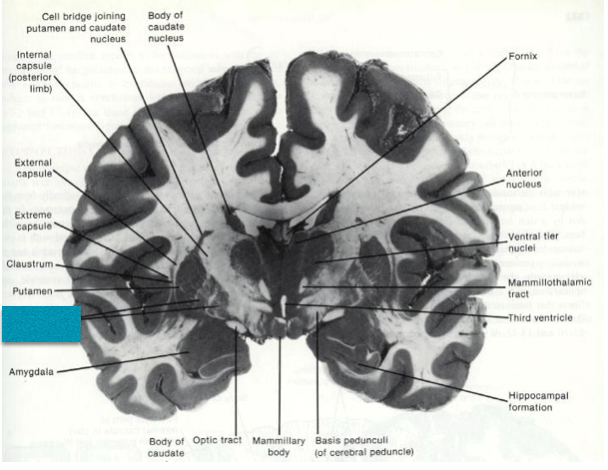

Fill in the blank.

Fill in the blank